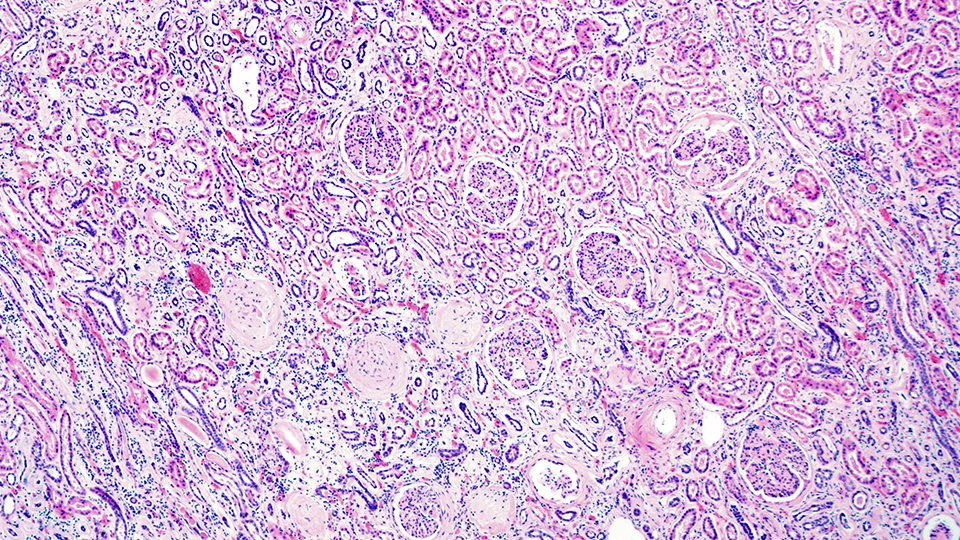

Les néphrites tubulo-interstitielles (NTIA) représentent la deuxième cause de maladie rénale intrinsèque. Si elles sont fréquentes, leur diagnostic est ardu car tant les manifestations cliniques que les analyses urinaires peuvent être pauvres, au point de se confondre avec le tableau de nécrose tubulaire. Aussi son diagnostic réclame une démarche raisonnée et le plus souvent le recours à la biopsie rénale lorsque celle-ci est possible, car elle seule est à même de poser formellement le diagnostic. Les enjeux sont majeurs et multiples. Faute de diagnostic prompt, et de prise en charge thérapeutique adéquate, il existe un risque élevé d’évolution vers la maladie rénale chronique. L’autre implication dérive de la démarche diagnostique étiologique. Les NTIA sont le plus souvent d’origine médicamenteuse. Cependant la sanction thérapeutique qui consiste en l’exclusion définitive du médicament suppose que le diagnostic ait été posé à bon escient. A côté des causes médicamenteuses, de nombreuses pathologies dysimmunitaires peuvent se traduire par une NTIA notamment la sarcoïdose, la maladie de Gougerot Sjögren et le TINU syndrome. Compte tenu des manifestations extra-rénales te leurs complications propres, ces diagnostics différentiels ne doivent pas être occultés. Enfin, plus rarement des pathologies lymphoprolifératives, des causes toxiques non médicamenteuses ou environnementales peuvent être identifiées.